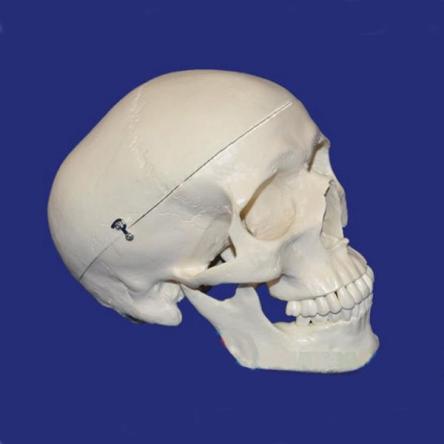

Детальная модель черепа человека A014 в натуральную величину с изображением всех детальных структур. Съемный свод черепа позволяет изучить внутреннее строение. Модель подходит для изучения в медицинских учебных учреждениях.

Модель разборная, из 3-ти частей.

Эта модель классического черепа объединяет качество, удобство использования с низкой ценой. Наглядное пособие представляет собой высокоточную копию натурального человеческого черепа.

Наша модель не просто состоит из 3-х частей (основной части, крыши и нижней челюсти), но и отличается тем, что имеет съёмные зубы. Нижняя челюсть подвижно соединена с основанием, крыша фиксируется на основании с помощью крючков.

При необходимости, крышу можно снять для изучения внутренней поверхности. черепа. Всё это делает данный муляж лучшим выбором для студентов-медиков, для школ и самообразования, к тому же являясь оригинальным медицинским подарком.

Модель изготовлена из лёгкого и прочного ПВХ. В отличии от натуральных черепов, модель долговечна и не требует каких-либо специальных условий работы с ней и хранения.